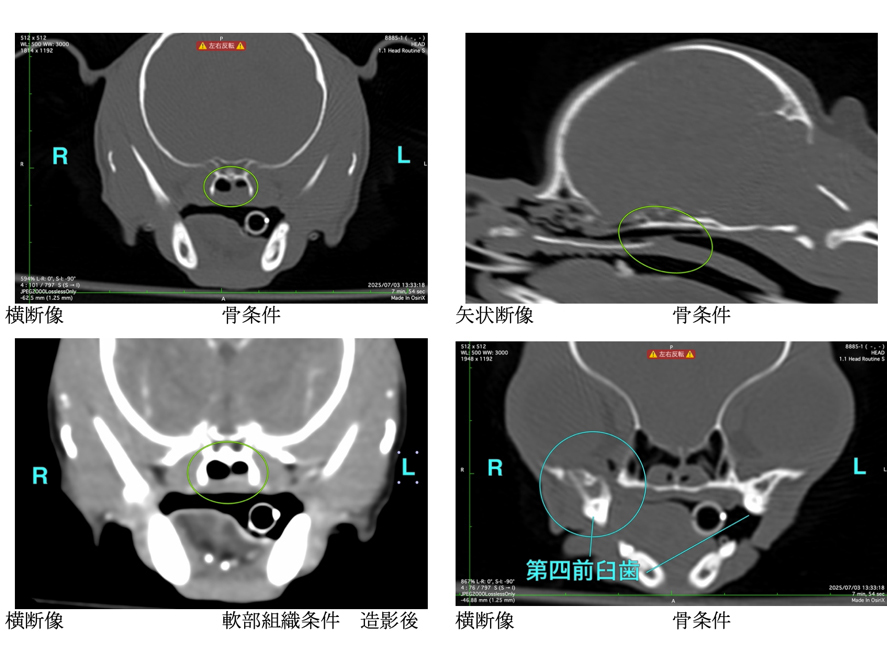

内視鏡検査の様子

内視鏡での鼻腔内の様子

摘出した異物